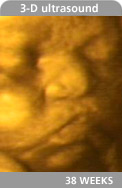

.38 weeks.be.coming.

How your baby's growing:

Your baby has really plumped up. She weighs about 6.8 pounds and she's over 19 1/2 inches long (like a leek). She has a firm grasp, which you'll soon be able to test when you hold her hand for the first time! Her organs have matured and are ready for life outside the womb.

Wondering what color your baby's eyes will be? You may not be able to tell right away. If she's born with brown eyes, they'll likely stay brown. If she's born with steel gray or dark blue eyes, they may stay gray or blue or turn green, hazel, or brown by the time she's 9 months old. That's because a child's irises (the colored part of the eye) may gain more pigment in the months after she's born, but they usually won't get "lighter" or more blue. (Green, hazel, and brown eyes have more pigment than gray or blue eyes.)